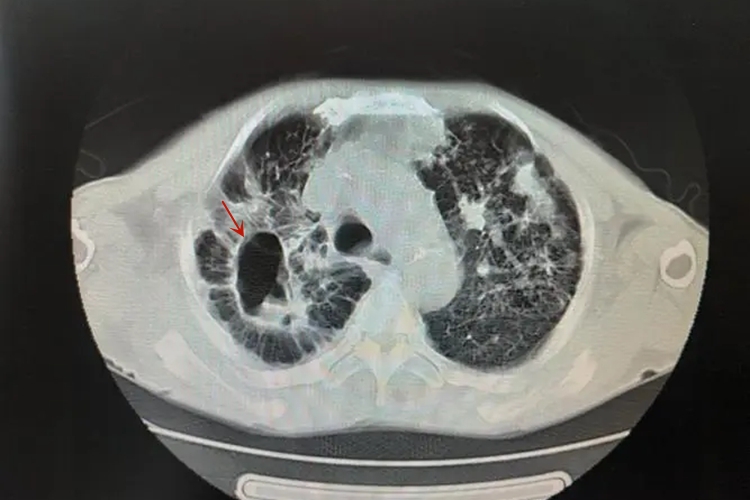

血行播散型肺结核:CT检查可更加清晰地显示粟粒性病灶,病灶直径1-3mm,大小、密度、分布均匀,边界较清晰。

继发性肺结核:具体表现多样,如斑片影、空洞、结核球等。影像学可出现局限性斑片影,见于两肺上叶尖段、后段和下叶背段,还可有肺段或肺叶大片致密性实变,其内可见一个或多个空洞,为虫蚀样空洞,边缘模糊。结核球为圆形椭圆形影,大小0.5-4cm不等,多为2-3cm,边缘清晰,轮廓光滑。